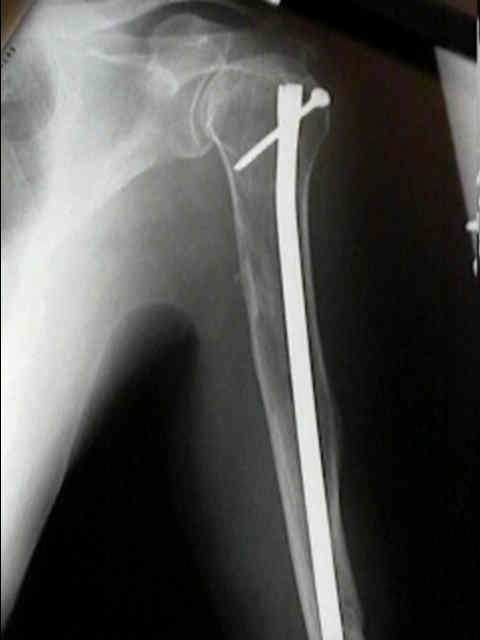

Humerus 10

Surgical Fixation

mmyl1 mmyl2